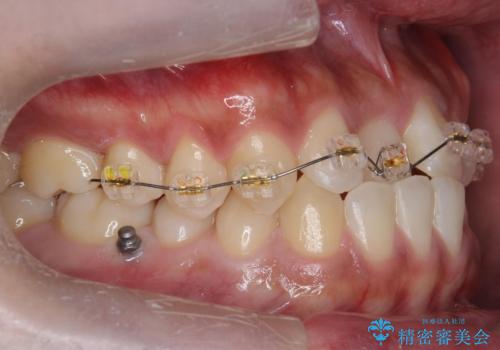

骨格性の受け口の矯正 部分ワイヤーで上の前歯を前に、 マウスピースで下の前歯を後ろに。

- インビザライン ワイヤー矯正

骨格性の受け口だったため、矯正用のミニスクリューを用いて、下の前歯をしっかり内側に入れました。

また、下顎はミニスクリューからマウスピースにゴムをかけて、下の歯並びが前に出ないようにして並べています。